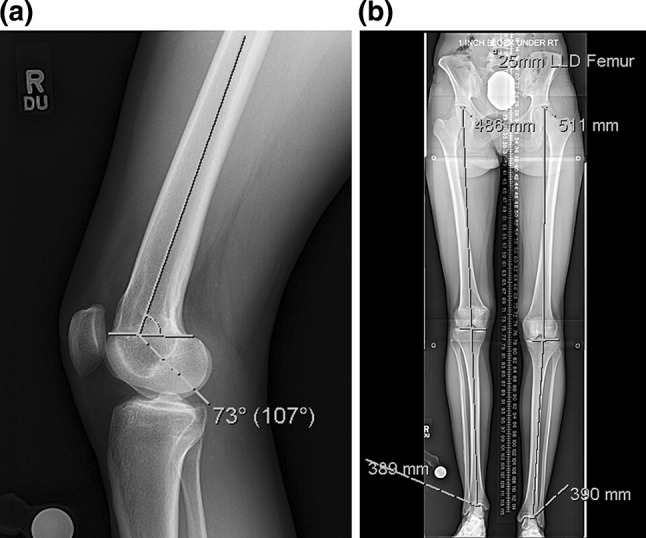

Fig. 1.

a This lateral radiograph of the knee shows a distal femoral flexion deformity of 10°. The posterior distal femoral angle (PDFA) measures 73° with the normal averaging 83°, b a 51 in., standing, bipedal radiograph with a 25-mm block under the right foot demonstrates a 25 mm leg length discrepancy originating from the right femur